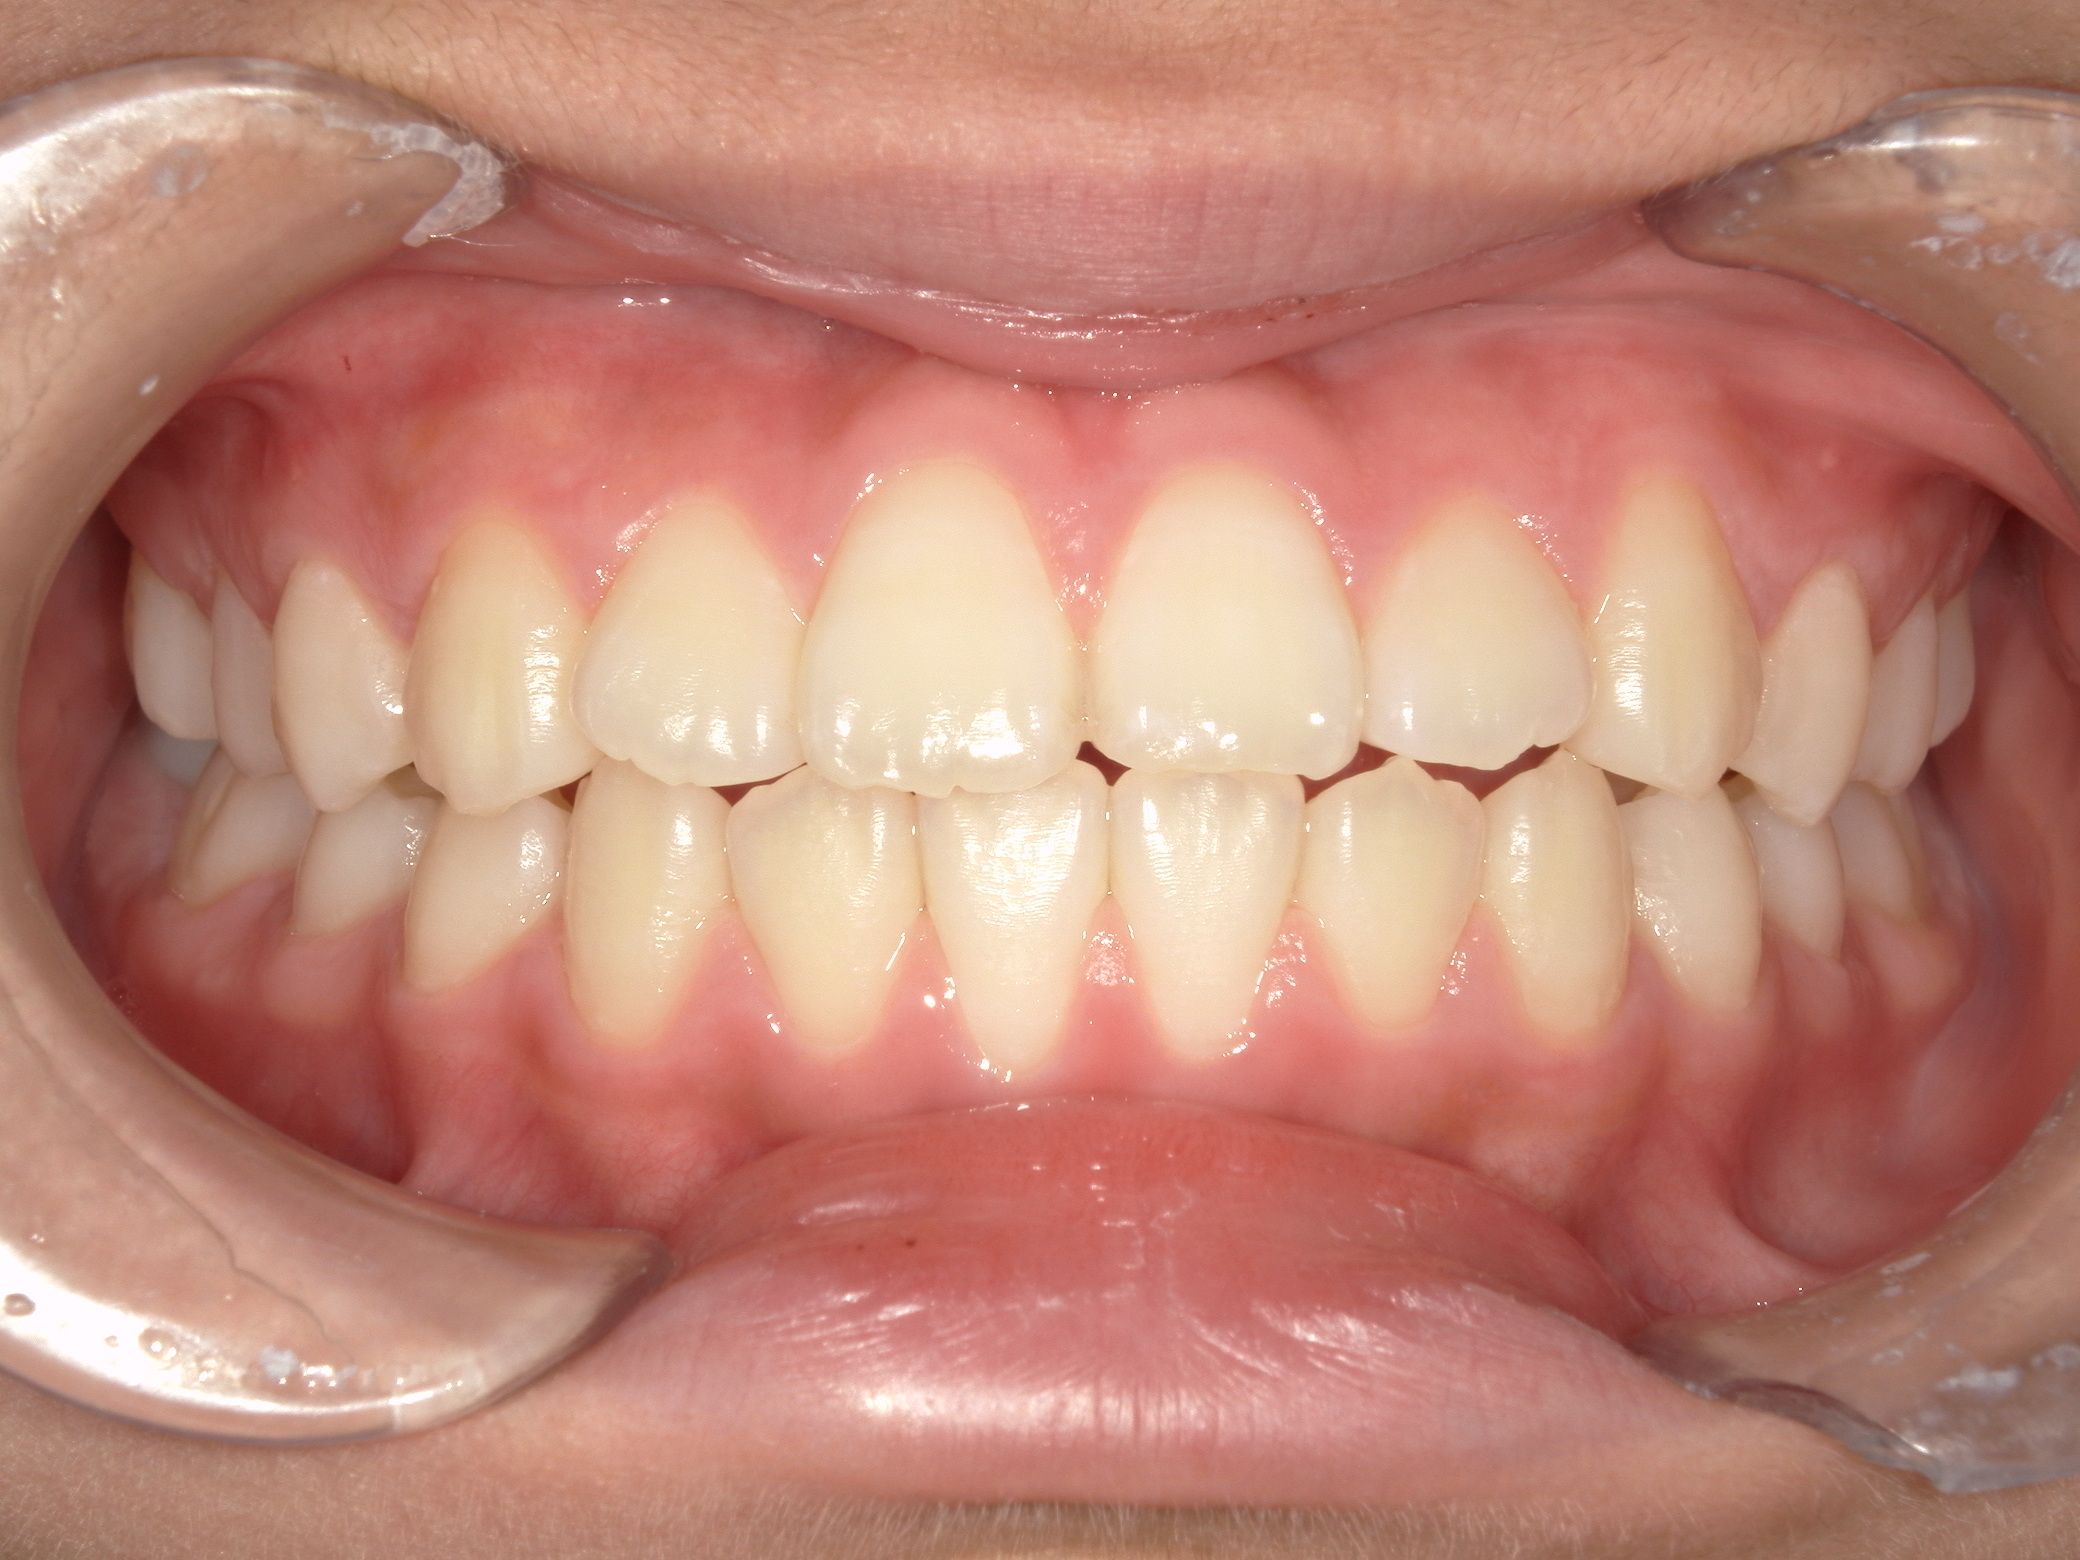

治療後After

ガタつきもなく、きれいなアーチになりました